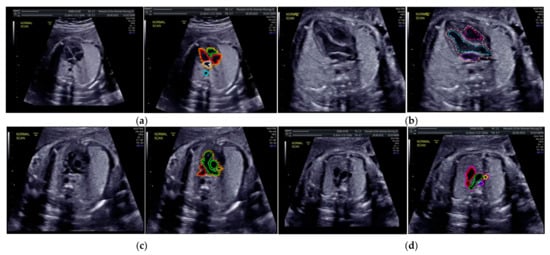

Images with inappropriate anatomical planes (cropped or badly captured) and those with calipers were excluded. The dataset composition was clearly imbalanced (some classes were more frequent than others), as is usually the case in real clinical scenarios. The sample of the raw ultrasound image was based on four views in normal anatomy, as depicted in Figure 2. In such sample, there are the left atrium (LA), left ventricle (LV), right atrium (RA), right ventricle (RV), ductus arteriosus (DUCT), superior vena cava (SVC), aorta ascendens (AoA), aorta descendens (Ao), and main pulmonary artery (MPA), whereas the sample of the raw ultrasound image of abnormal anatomy structure, with the three heart defects such as ASD, VSD, and AVSD condition, is compared to normal anatomy structure in Figure 3. In the abnormal structure, there are hole (H) as heart defect in each condition. Each defect has the variation of hole size; such hole size indicates the disease severity. However, in this study, we only detected the hole, without measuring the hole size.

Figure 2.

Fetal heart scan in four standard views of normal anatomy: (a) 4CH; (b) LVOT; (c) RVOT; and (d) 3VT.

Especially for heart defect detection, only 4CH view was used to analyze ASD, VSD, and AVSD images. Annotated images indicate the position of defect in the atrium, ventricle, or both of them. Figure 4 depicts the sample of annotated images for a standard view of 4CH, 3VT, LVOT, and RVOT, and Figure 5 shows the sample annotated images of defect position in ASD, VSD, and AVSD. Finally, the whole annotated images are labelled as the ground truth database, and it was saved in the JSON file format (json).

Figure 4.

The sample of annotated images by maternal–fetal clinician for standard fetal heart view segmentation in (a) 4CH (orange: view, cyan: AoA, red: LA, grey: RA, green: LV, and red: RV); (b) LVOT (orange: view, cyan: LA, purple: RV, and blue: LV); (c) RVOT (orange: view, green: MPA, red: DUCT, and yellow: SVC); and (d) 3VT (purple: view, yellow: AoA, green: SVC, and red: DUCT); based on normal anatomy.